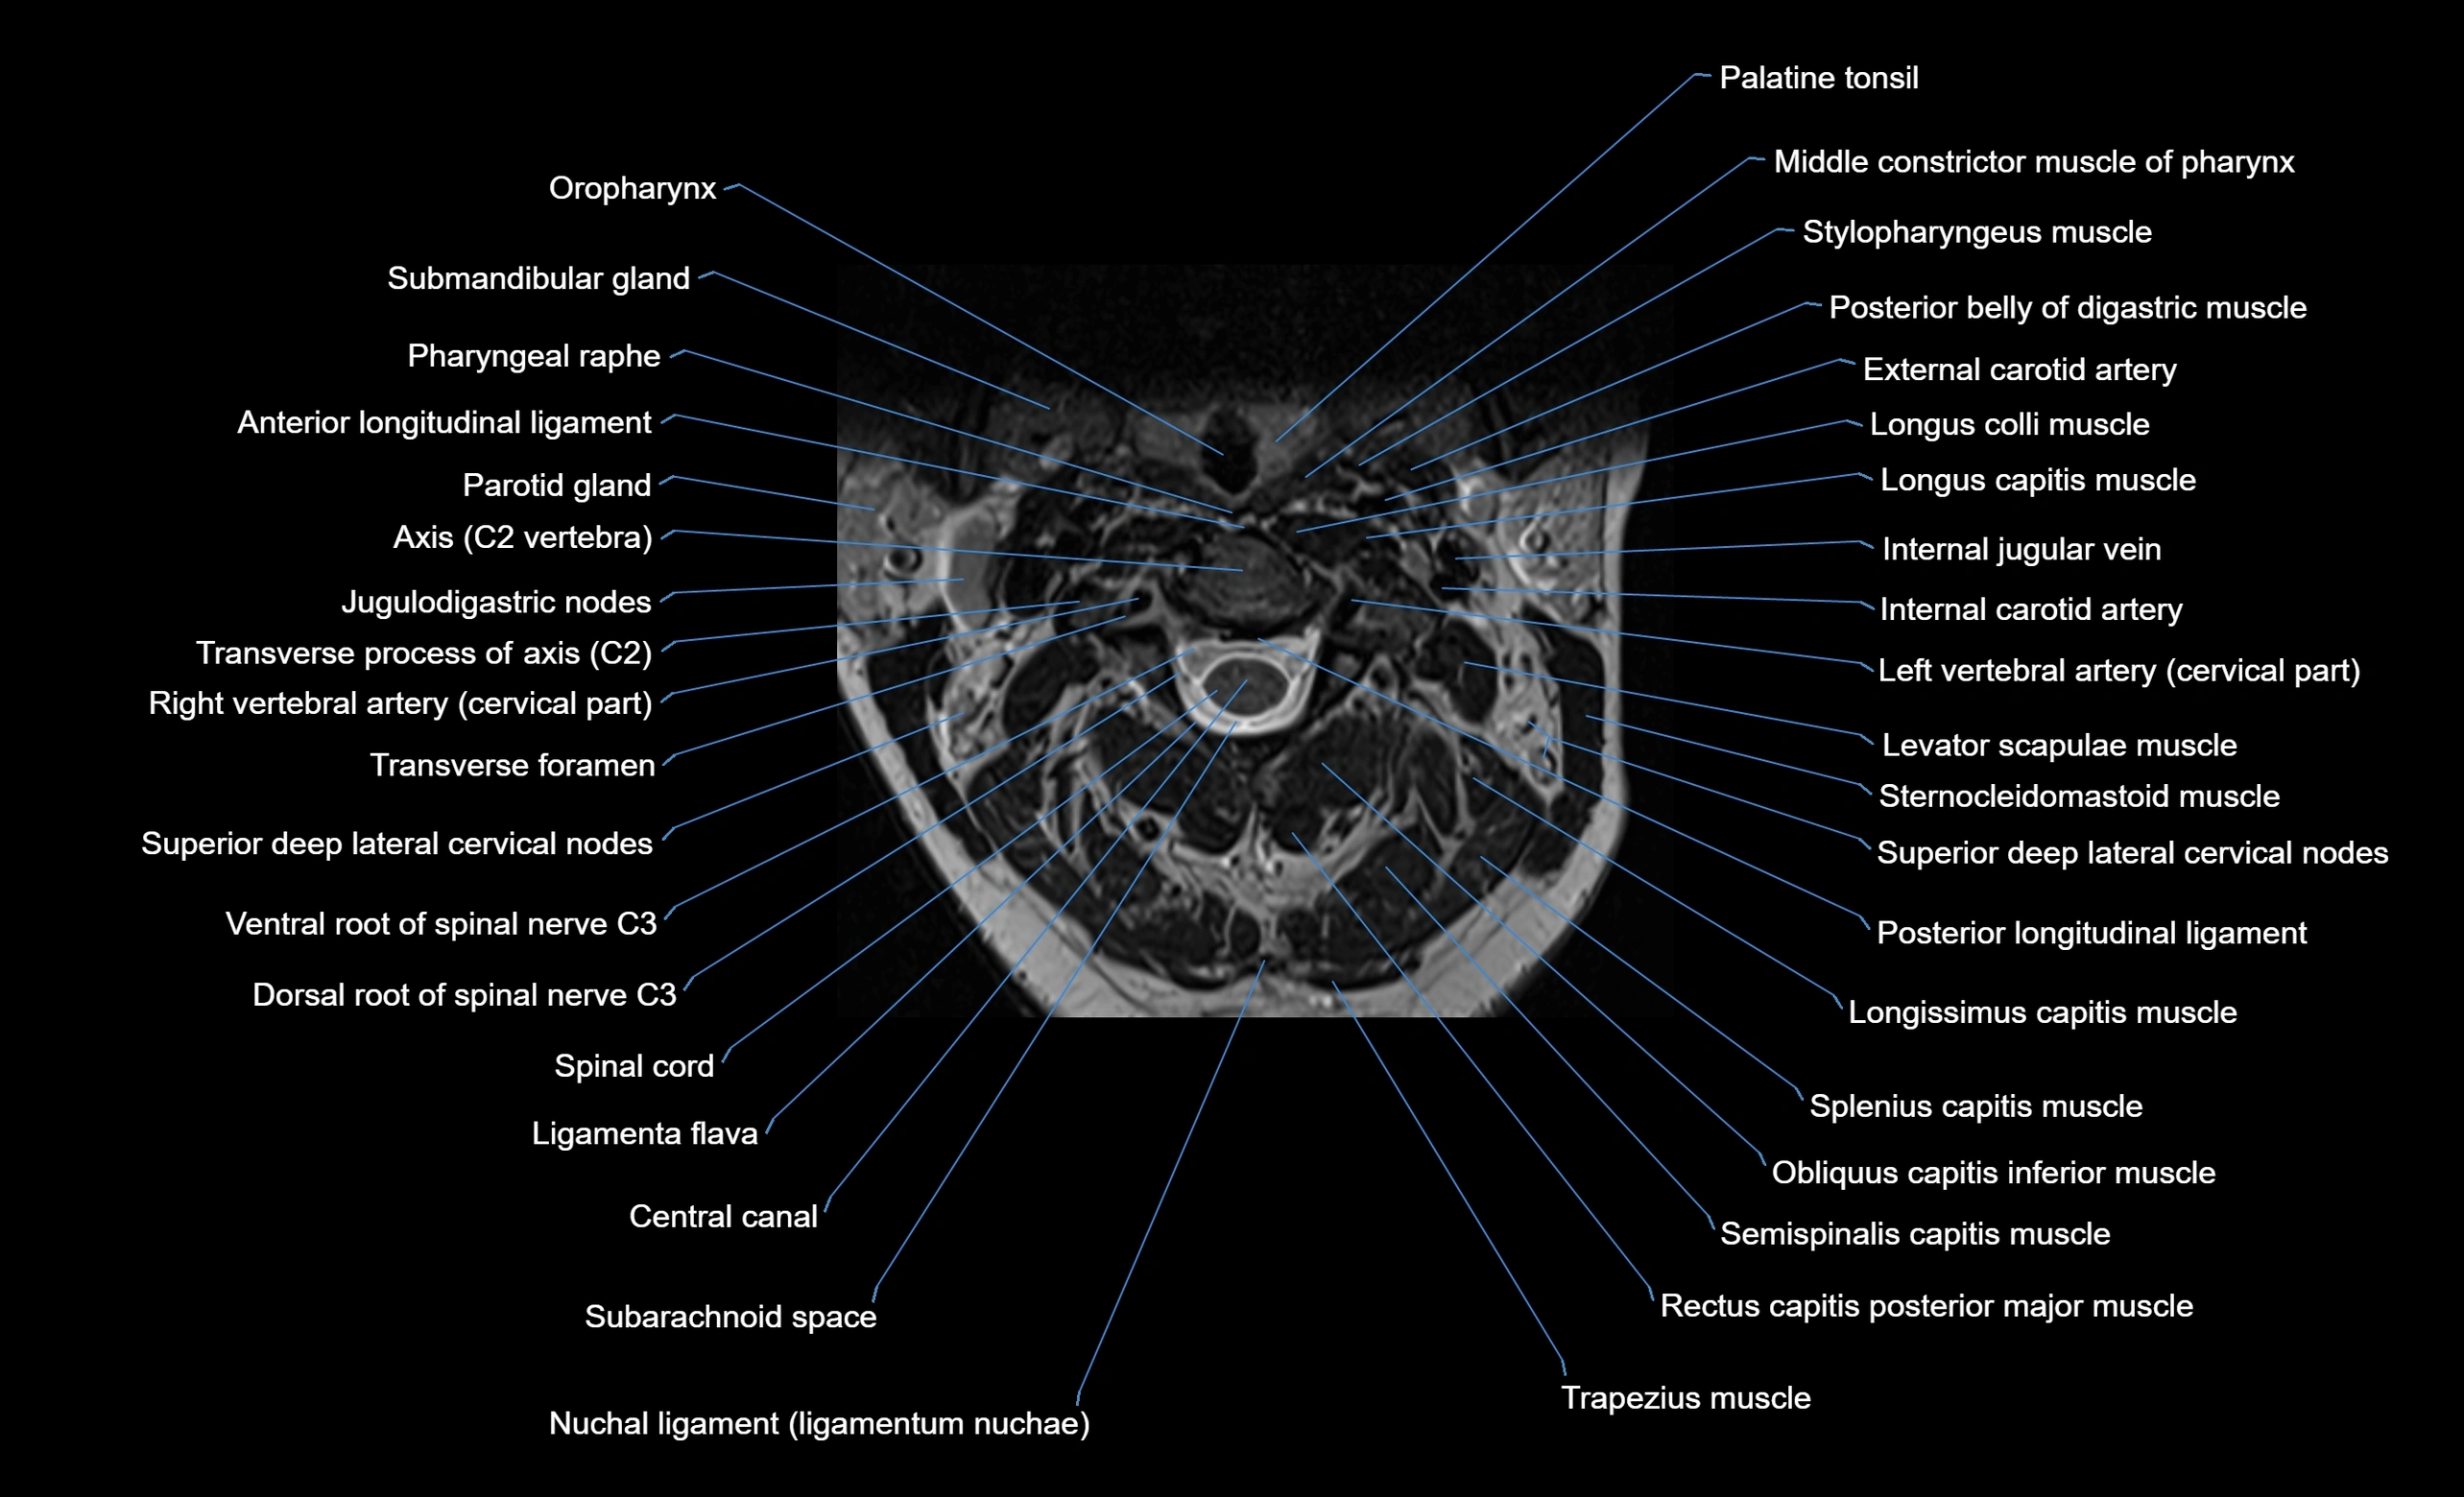

MRI image

image